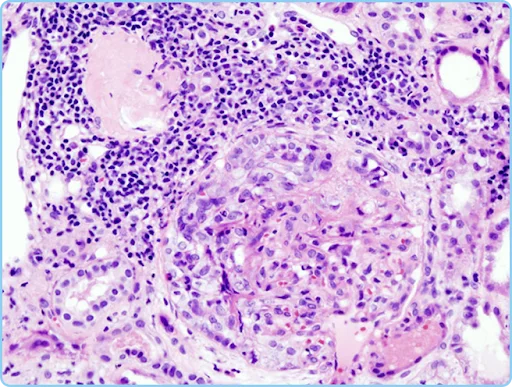

Q16. A 28-year-old female presented to the emergency department with severe fatigue, leg swelling, and decreased urine output following an upper respiratory infection two weeks ago. Urinalysis shows hematuria and proteinuria. The histopathological findings of renal biopsy are shown below. All of the following are associated with Type II of this condition, except,

- Henoch-Schönlein Purpura

- Systemic lupus erythematosus

- Wegener granulomatosis

- Berger’s disease

Ans. 3) Wegener granulomatosis